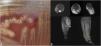

A) Colonias β-hemolíticas en agar TSA con 5% de sangre de carnero (incubación 24h, 5% CO2). B) Colección en cara posterior de la pierna (diámetros de 8×5×2cm) compatible con absceso (flecha inferior), colección pretibial (1,7cm) en tercio medio y otras colecciones a nivel distal (círculo). Colección en la región de la articulación en relación con el tendón y vaina flexora del primer dedo de 2cm (flecha superior). También se observó alteración renal de señal en relación con osteítis u osteomielitis incipiente en maléolo externo, en relación con el trayecto de los tornillos retirados a lo largo de 10cm y con restricción del coeficiente difusión, en ambos casos abscesificadas.

La muestra de material de osteosíntesis se introdujo en un recipiente con medio de enriquecimiento tioglicolato, que se incubó a 37°C en aerobiosis durante 24h y posteriormente se realizó tinción de Gram, y se inoculó en agares chocolate y Brucella. Las muestras de los abscesos se sembraron en agares chocolate, TSA con 5% de sangre de carnero, McConkey, CNA y Brucella. En todas las tinciones de Gram se identificaron cocos grampositivos en cadena y parejas. A las 24 h crecieron colonias β-hemolíticas en los agares TSA (fig. 1A), identificadas como Streptococcus canis (S. canis) mediante espectrómetro de masas MALDI-TOF (Bruker, Massachusetts, Estados Unidos) con un valor de 2,15. La susceptibilidad antibiótica se estudió mediante el panel SMIC-ID-11 en el sistema BD PhoenixTM (Becton Dickinson, Nueva Jersey, EE.UU.) AP. La cepa resultó sensible a penicilina (CMI ≤ 0,03mg/l), eritromicina (CMI=0,125mg/l), clindamicina (CMI=0,06mg/l), tetraciclinas (CMI ≤ 0,5mg/l), vancomicina (CMI ≤ 0,5mg/l), teicoplanina (CMI ≤ 1mg/l) y daptomicina (CMI ≤ 0,25mg/l), mientras que mostró sensibilidad con dosis incrementada para levofloxacino (CMI=1mg/l) (criterios EUCAST; www.eucast.org).

El paciente empezó a recibir tratamiento antibiótico por vía IV con ceftriaxona (2g/24h) y mejoró sustancialmente, aunque después de 4 días comenzó con edema y eritema en la parte posterior de la pierna derecha. Mediante resonancia magnética se hallaron colecciones a lo largo de la misma (fig. 1B) que fueron drenadas y las muestras fueron cultivadas (6 muestras). En la tinción de Gram de 2muestras se observaron cocos grampositivos en parejas, aunque no hubo crecimiento. Tras reinterrogar al paciente, este negó tener contacto con animales en los últimos años.